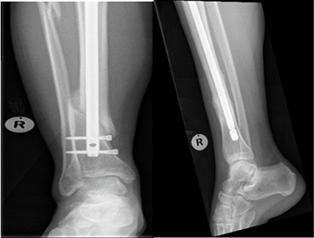

There were 61 males (61%) and 39 females (39%). The median age of the participants was 36 (47-27) years, ranging from 18 to 77 years. A total of 80 patients (80.0%) were treated with intramedullary nailing, 20 (20.0%) treated with plating. In the plated group, 15 were treated with anterolateral plates (75%) and five treated with medial plates (25%). Five of the plate cases were more distal and comminuted and not amenable to intramedullary nailing. The immediate post-operative AP X-Ray views showed that 73 participants had an acceptable alignment (73%) and 27 had malalignment (27%) (Figure 3 & 4). Lateral view showed that 98 participants had acceptable alignment, with unacceptable alignment in only two patients.

Figure 3 Malunion post IMN.

Figure 4 Malunion post IMN.